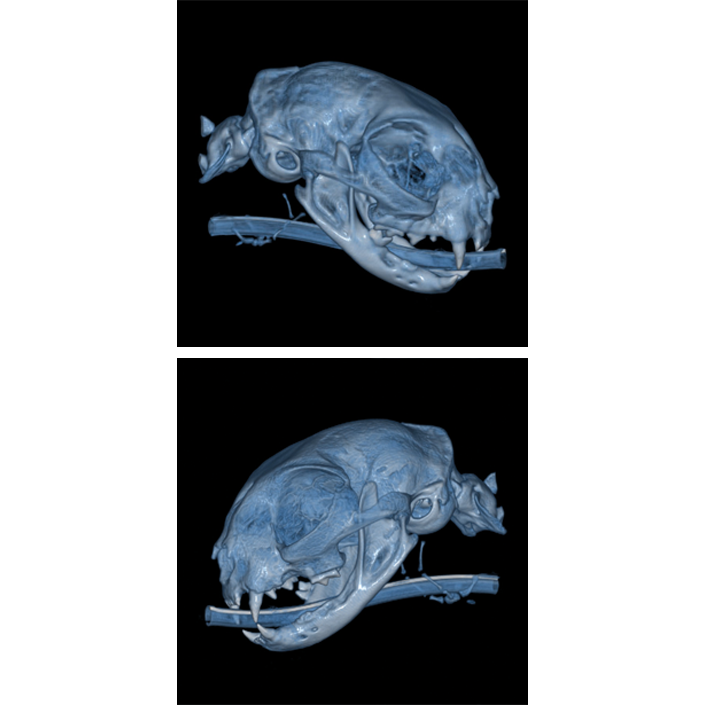

Das NewTom 5G XL VET Compact ist die ideale Lösung für Praxen mit geringem Platzangebot.

Dieses CBCT vereint die Vorzüge des NewTom 5G XL mit einem speziell entwickelten Carbon CBCT Tisch.